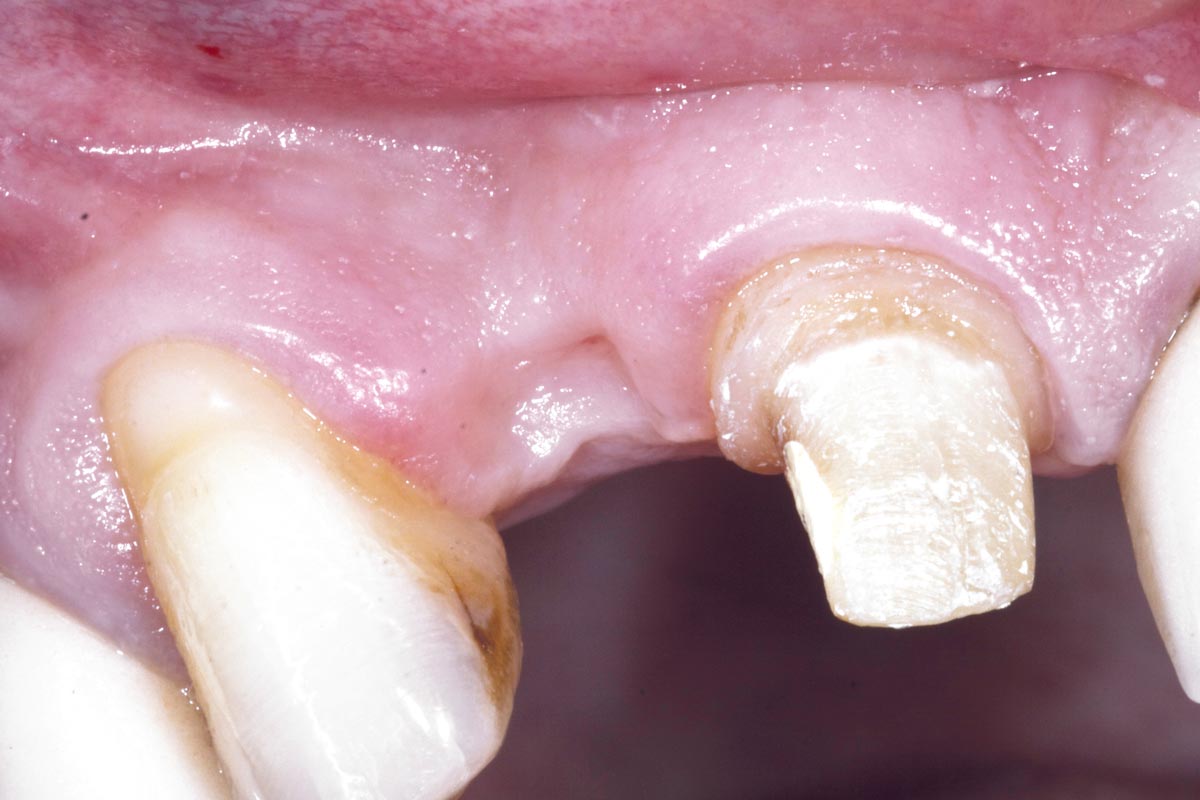

3/19 - Fracture of tooth while extractionBone augementation with maxresorb® - Dr. R. Cutts

4/19 - Site after extractionBone augementation with maxresorb® - Dr. R. Cutts

Clinical situation before extraction